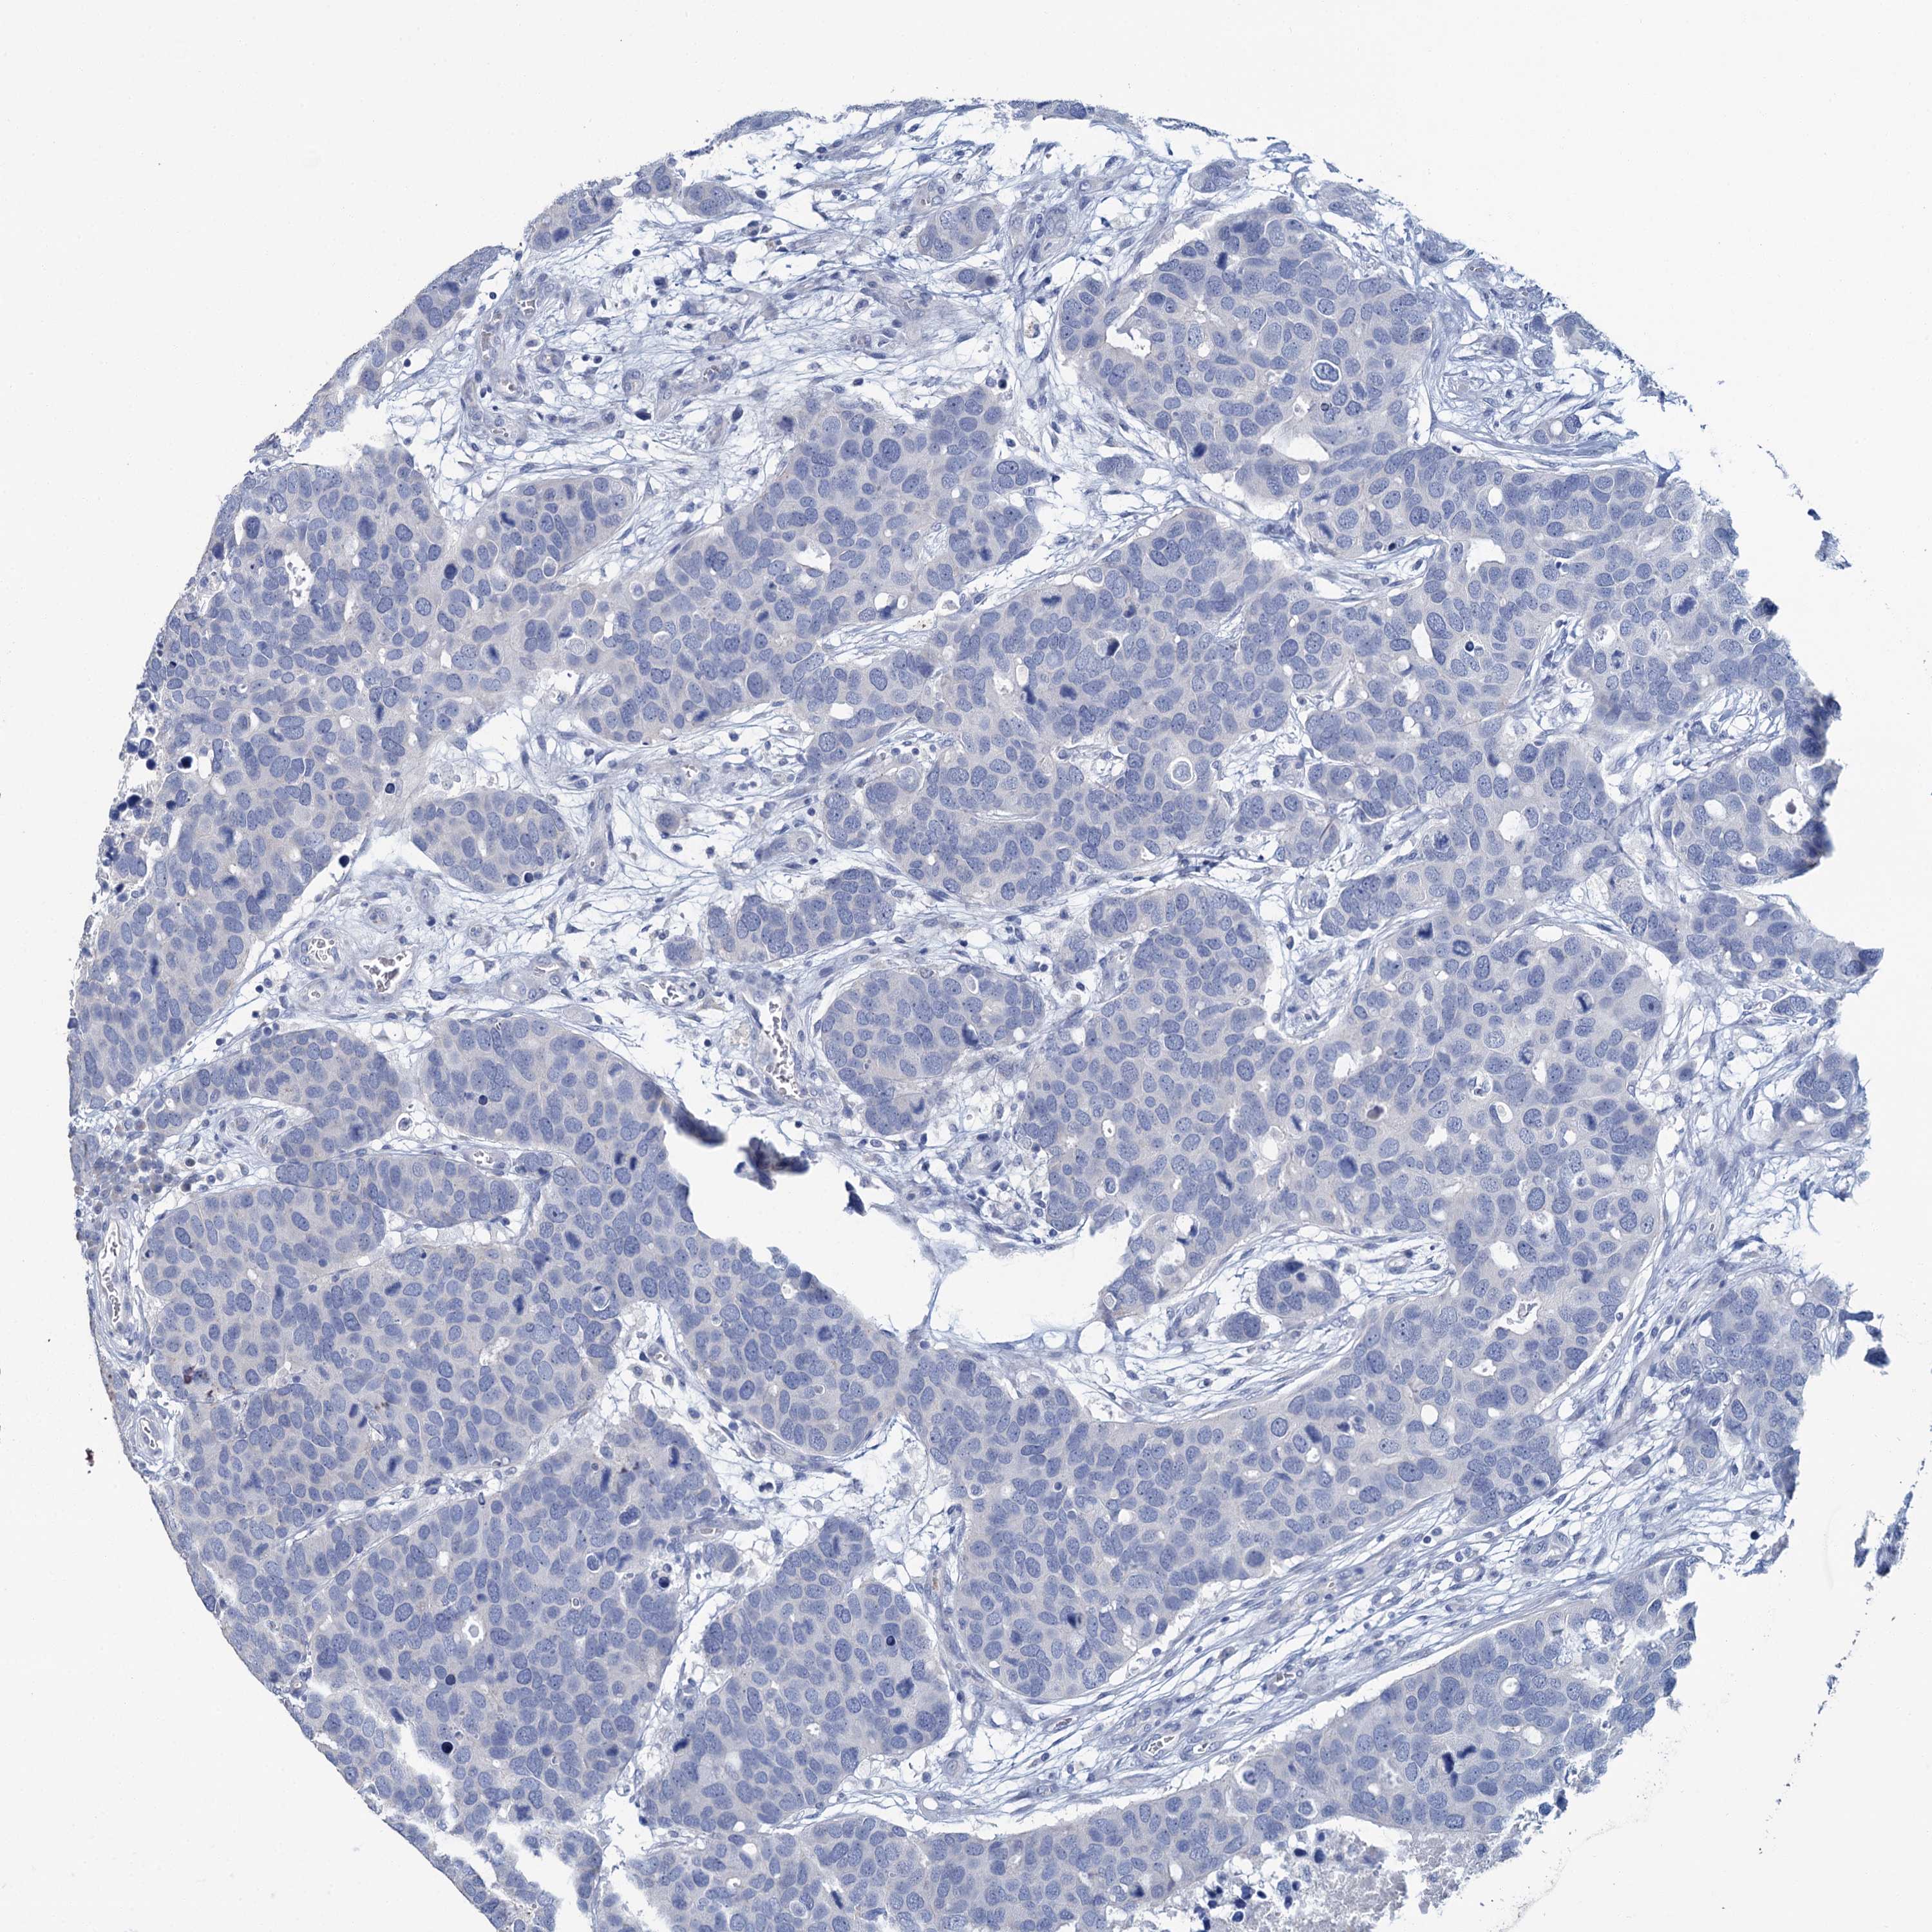

CANCER BREAST CANCER Show tissue menu

Breast cancer

Human cancer

SNCB is not prognostic in Breast Invasive Carcinoma (TCGA)